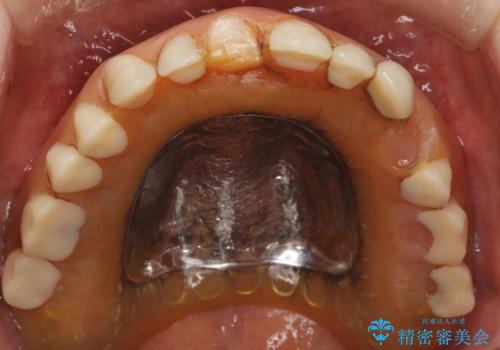

- 上の入れ歯の歯がとれてしまったこと・ゆるくてはずれてしまうことを主訴に来院された患者様です。

精査したところ、長年使用されていた入れ歯は劣化し、人工歯の脱離及び適合不良を認めました。

患者様のご希望により、上顎金属床義歯の新製を行いました。

適合を良くするため、咬座印象も行いました。